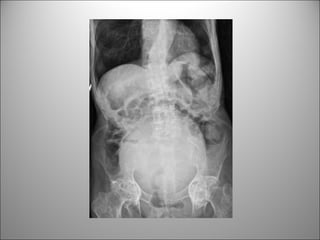

PATRÓN DE GAS INTESTINAL

• Contraste natural

• Puedo diferenciar entre Int. delgado y cólon?

– Si, principalmente si hay distensión

Dato clave:

REGLA DEL 3/6/9

3 cm Int. Delgado

6 cm Colon

9 cm Ciego